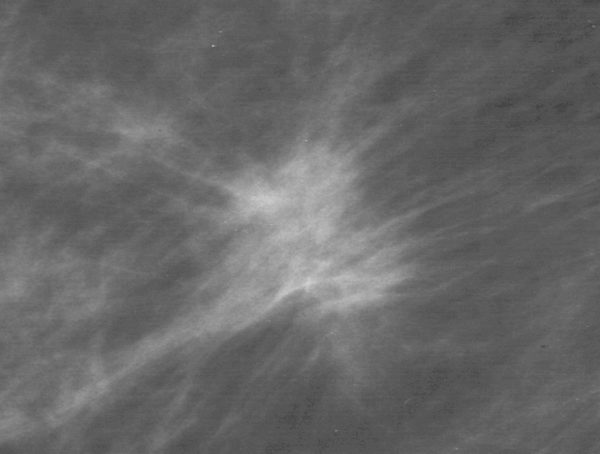

Das Bild zeigt ein Mamma - Karzinom mit strahligen Ausläufern.